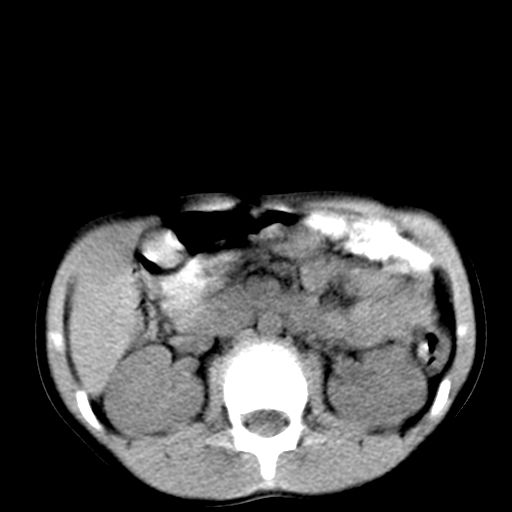

腹部好象未见异常。

腹部ct平扫未见明确异常

腹部ct平扫不能提示哪里有病变。